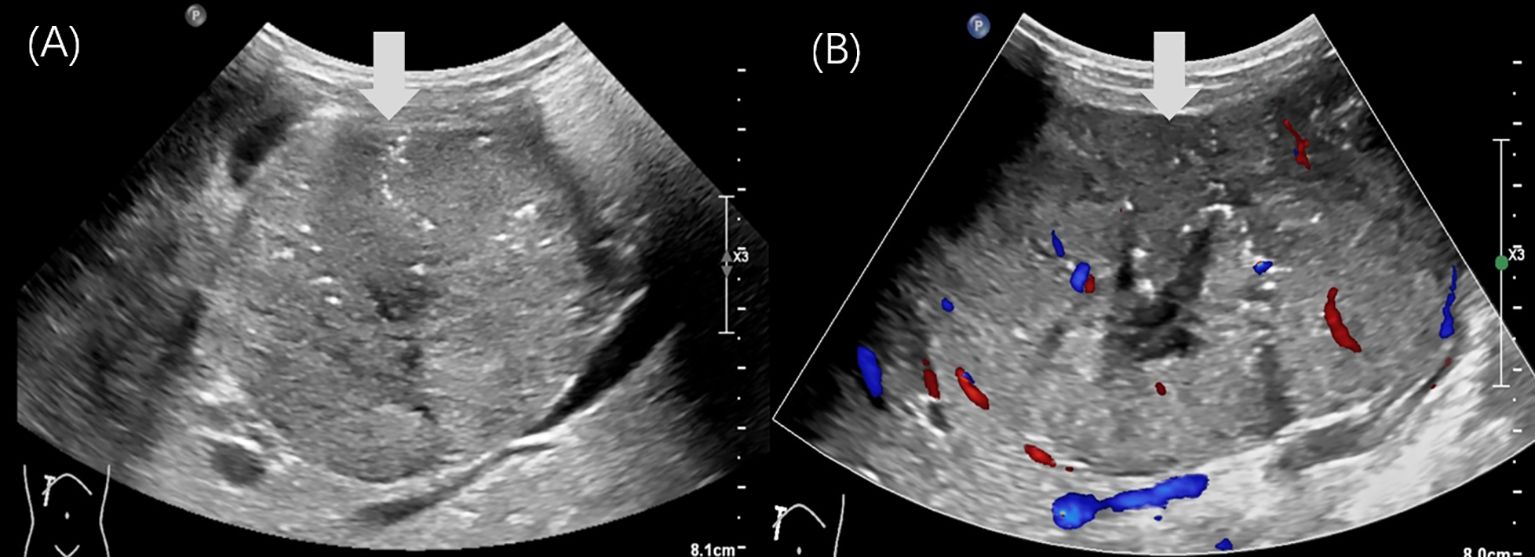

Pancreatoblastoma (PB) is a rare malignant neoplasm of the pancreas, primarily affecting children. While some reports have described the imaging characteristics of PB, detailed descriptions of its ultrasound (US) and contrast-enhanced ultrasound (CEUS) features in children are limited. We reported two cases of PB admitted to our hospital with detailed ultrasonographic features. The first case involved a 14-year-old girl who presented with intermittent, unexplained epigastric pain. CEUS revealed a hypoechoic mass with heterogeneous hyperenhancement in the pancreatic head. She underwent pancreaticoduodenectomy and remains disease-free to date. The second case was a 4-year-old boy with a palpable, unexplained mass in the right upper abdomen. US identified a well-defined, heterogeneous mass in the epigastric region with internal point-like hyperechoic areas. The intraoperative US showed portal vein cancer thrombus. He underwent tumor resection along with reconstruction of the portal and superior mesenteric veins. He subsequently received chemotherapy and remained disease-free to date.